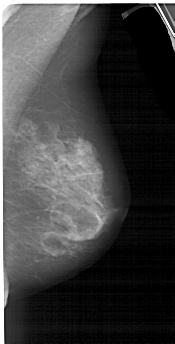

A_1553_1.LEFT_CC

RIGHT_CC LINES 4936 PIXELS_PER_LINE 2476 BITS_PER_PIXEL 12 RESOLUTION 43.5 NON_OVERLAY